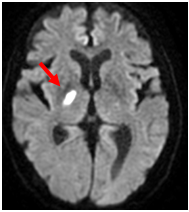

【ラクナ梗塞】

脳の深いところにある直径1mm以下の細い血管がつまるものです。梗塞自体はとても小さいものですが手足の動きに大事なところが障害されるため手足の麻痺が重くなることがあります。高血圧や糖尿病、喫煙などが原因で起きるのが多いといわれています。約2~3割の症例で症状が進行することがあります。

MRI;拡散強調画像

【MRI;拡散強調画像】

MRI;FLAIRA

【MRI;FLAIR】

MRIでは1.5cm以下の小さな梗塞として描出。